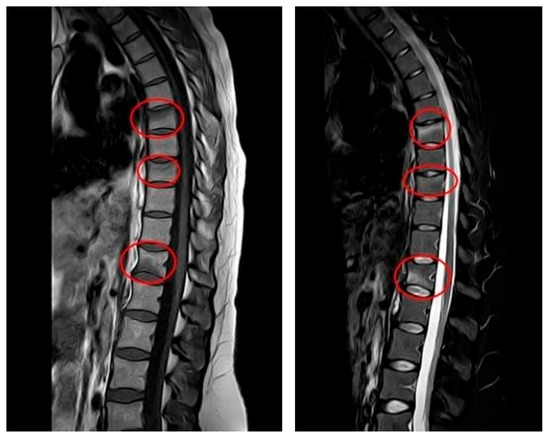

After initiating conservative treatment, the MRI after 90 days was carried out and the results showed a complete disappearance of the vertebral compression fractures. All previously identified fractures were stabilized and the previously noted edematous band in the spongy part of the vertebral body had disappeared (Figure 2).

Figure 2. MRI at follow-up (April 2024, at four-month postpartum follow-up): repeat sagittal MRI showing resolution of edema and stabilization of previous vertebral compression fractures. Vertebral alignment is preserved with no evidence of new pathology. Subfigure (A) on the left shows T1-weighted sequence on the left. Subfigure (B) shows T2-weighted sequence on the right.

The therapeutic regimen included continuation of pharmacological management with calcium and vitamin D supplementation and weekly intramuscular clodronate administration for six months. Activity restrictions regarding weight-bearing and lactation were maintained. Following the second MRI findings, the rehabilitation protocol was modified accordingly.